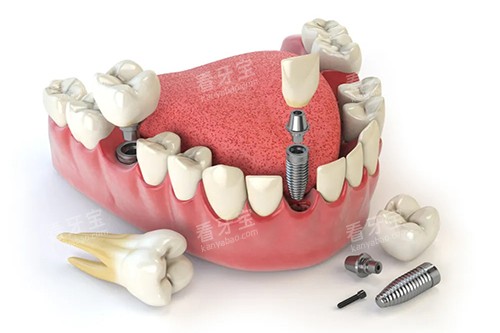

在种植牙领域,AI智能化导航种植技术能够精密定位种植体的位置和深度,降低手术风险,提高种植成功几率,减少患者的痛苦和修复时间。